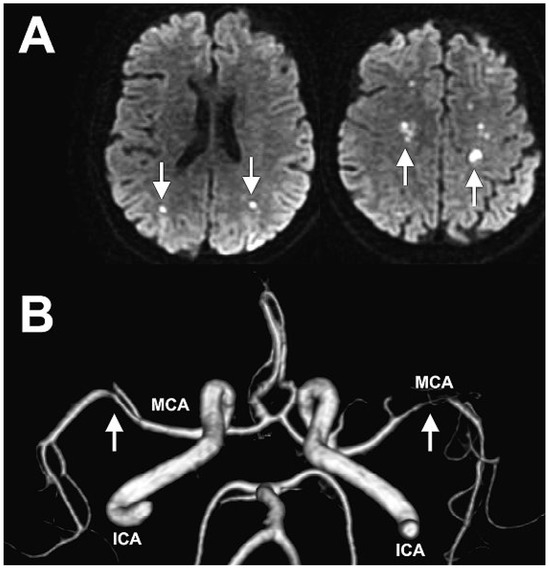

A CT-scan of the brain was performed for further evaluation of the neurological symptoms and showed pansinusitis and multifocal vascular lesions in the brain. The diffusion-weighted MRI sequences revealed multiple small acute brain infarcts (Figure 2A) and the MR angiography showed extensive stenosis of both middle cerebral arteries (Figure 2B).

Figure 2.

A Multiple small acute brain infarcts (white arrows) on diffusion-weighted imaging(DWI) sequences. B MR angiography showing extensive stenosis of both middle cerebral arteries(white arrows). ICI = internal carotid artery; MCA = middle cerebral artery.